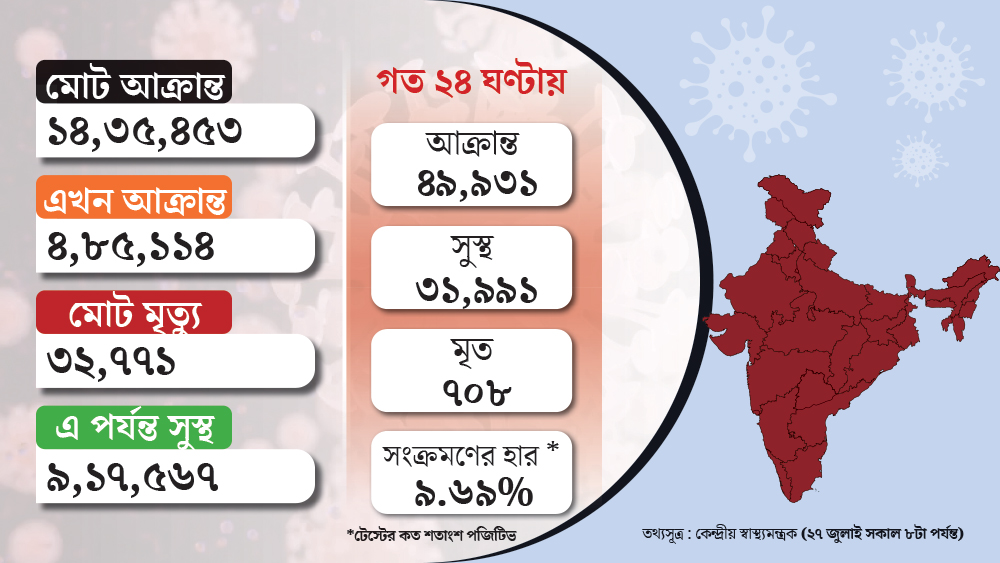

২৪ ঘণ্টায় বৃদ্ধি প্রায় ৫০ হাজার, দেশে মোট আক্রান্ত ১৪ লাখ ছাড়াল